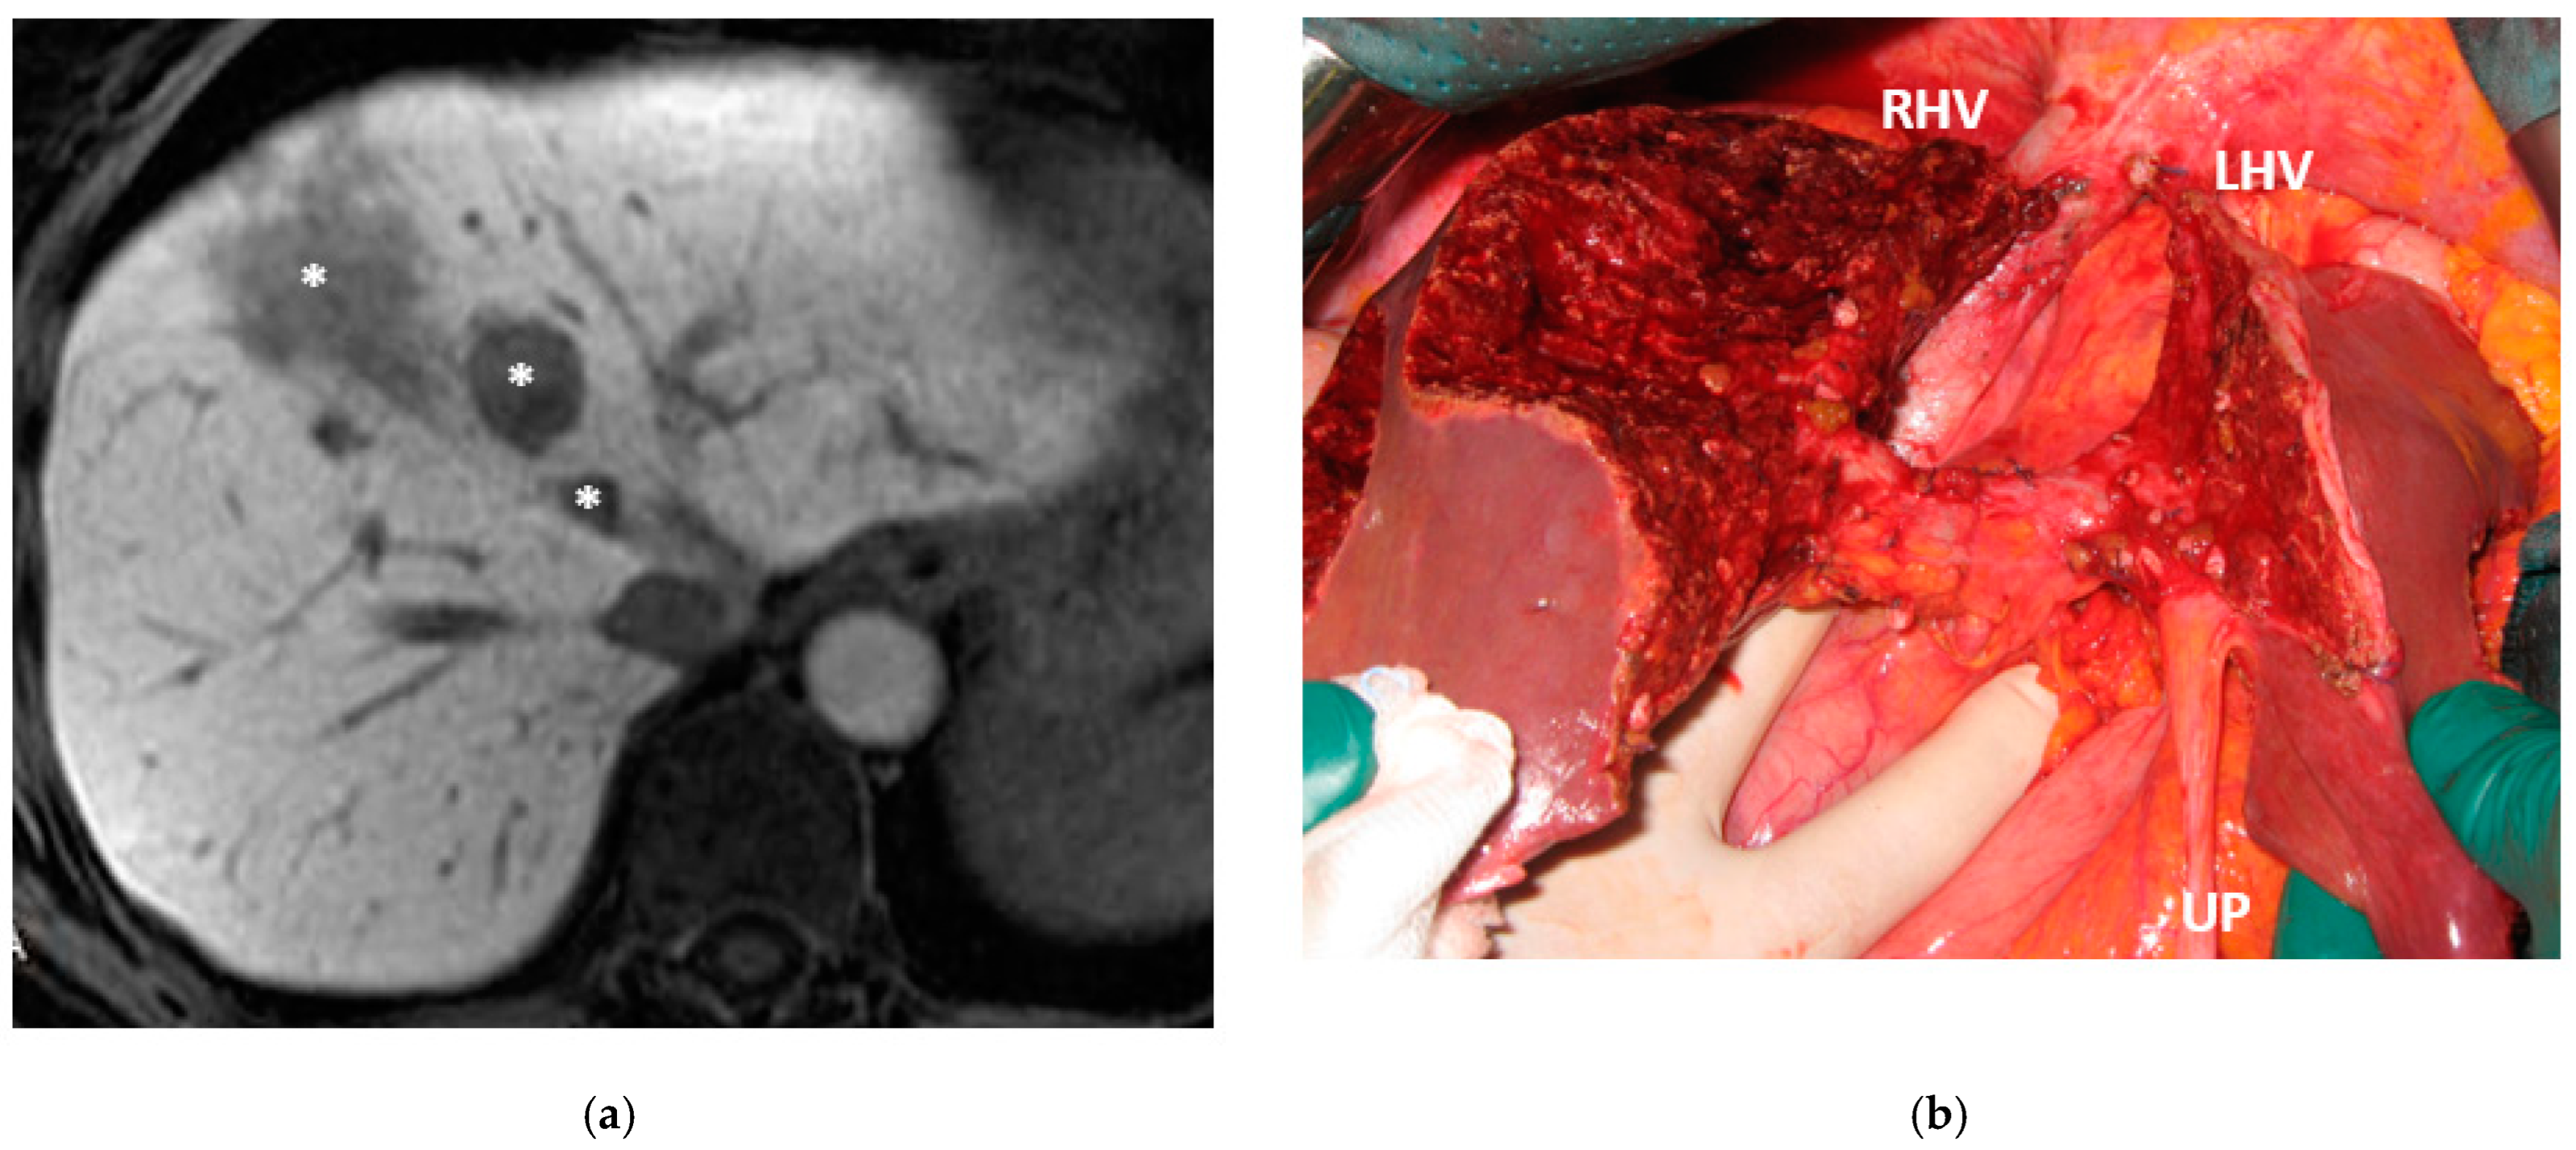

Liver partition was obtained with a major mesohepatectomy in two cases with anatomical resection of S1/S4/S8 (en-bloc with biliary tree in one, see Figure 5).

Two out of eight patients with unresectable disease relapse are still alive although with evident disease: one patient 18 months after e-ALPPS performed as a “liver first” strategy for 27 synchronous CRLMs with left colon adenocarcinoma and interaortocaval lymph nodes, then followed by a left hemicolectomy and interaortocaval lymphadenectomy, who experienced an extrahepatic recurrence 3 months after surgery; and one patient 38 months after a major MLP associated with a three-duct jeujunostomy (performed for two CRLMs infiltrating the confluence of left and right bile ducts up to S8 bile duct and with modest dimensional increase of CRLM after 47 cycles of FOLFIRI + Bevacizumab across several reintroductions, Figure 5), with hepatic and extrahepatic recurrence 12 months after surgery.

Figure 5. This is a case of liver partition obtained with a major mesohepatectomy performed for CRLM that behaves as biliary cancer infiltrating the confluence of left and right biliary ducts up to S8 duct; this is a highly challenging location for CRLMs at high risk of worsening patient’s quality of life and hampering chemotherapy administration due to jaundice; for this reason, liver resection was performed despite a modest dimensional increase of CRLMs after several courses of FOLFIRI + Bevacizumab administered over three years and after an initial complete radiological response. (a) Intraoperative field with the identification of the two liver transection lines for liver partition (yellow dotted lines). (b) Liver partition at the end of resection of S1/S4/S8 en-bloc with extrahepatic biliary tree resected up to left duct, S5 duct and posterior duct. Three-duct jeujunostomy was performed. Thirty-eight months after liver partition, the patient is under chemotherapy treatment (no jaundice) with stable and asymptomatic extrahepatic and hepatic recurrence. Abbreviations: CRLM: colorectal liver metastases; S: segment; RHV: right hepatic vein; UP: umbilical portion.